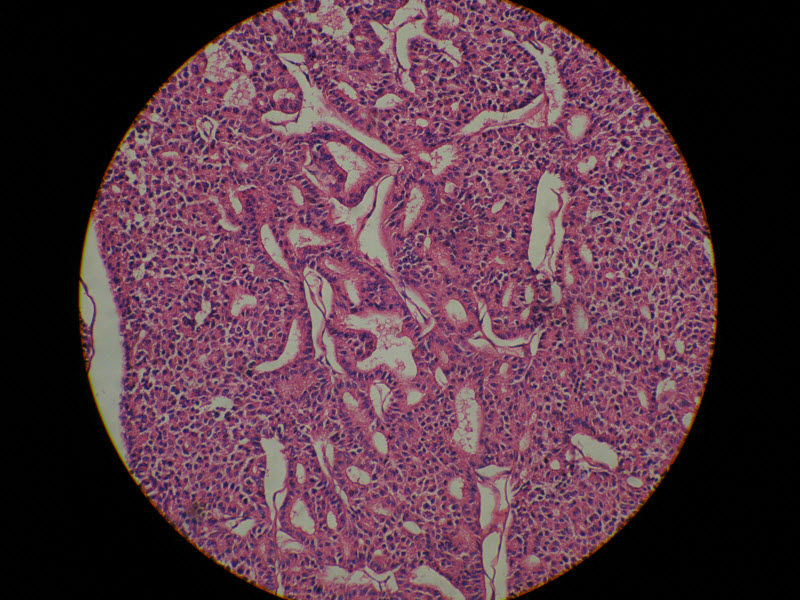

肾脏肿瘤,请教诊断!图1

名称:图1

描述:10倍

肾脏肿瘤,请教诊断!图2

名称:图2